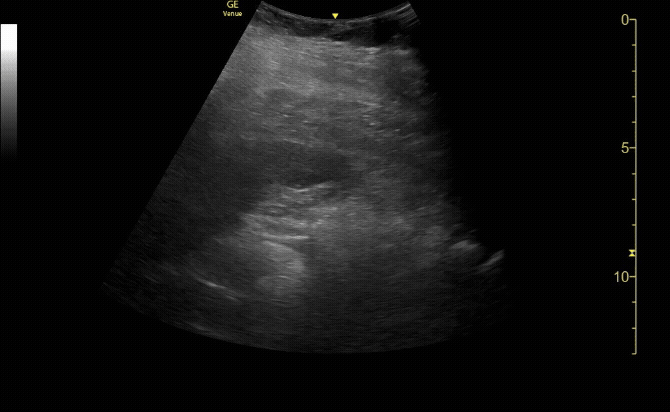

Gallbladder wall measuring less than 0.3cm

c/o John Tucker, MD